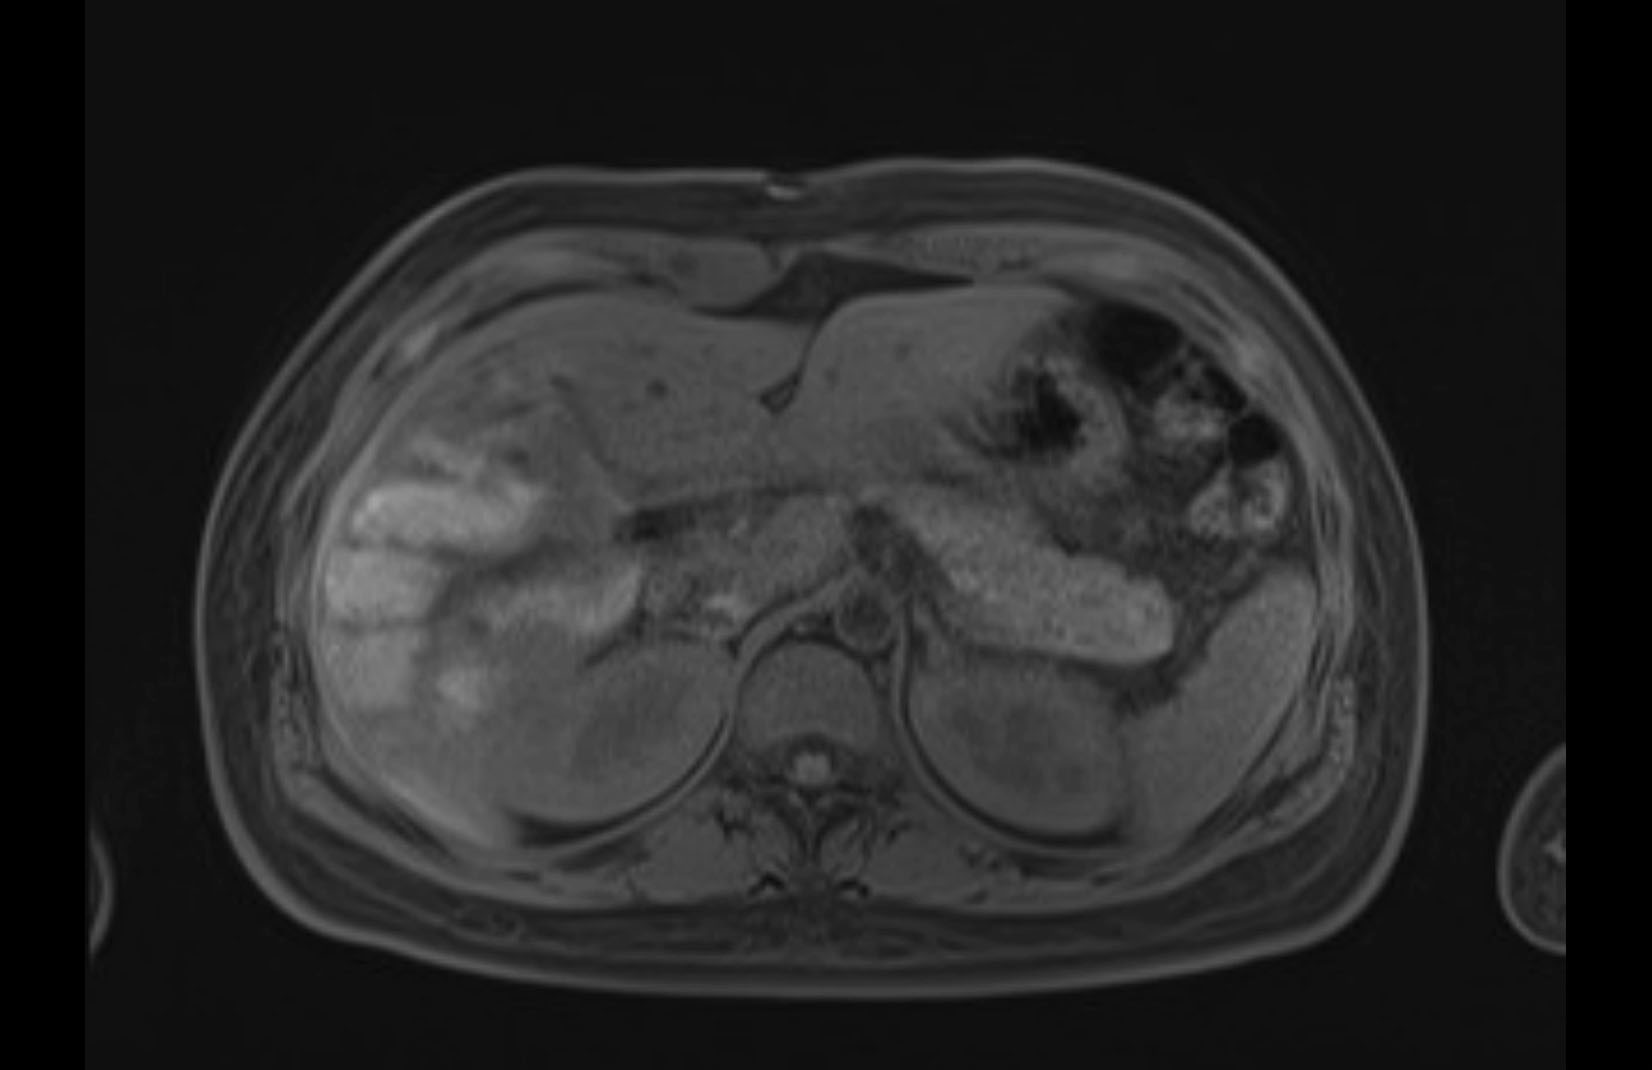

MRI T1

MRI T2